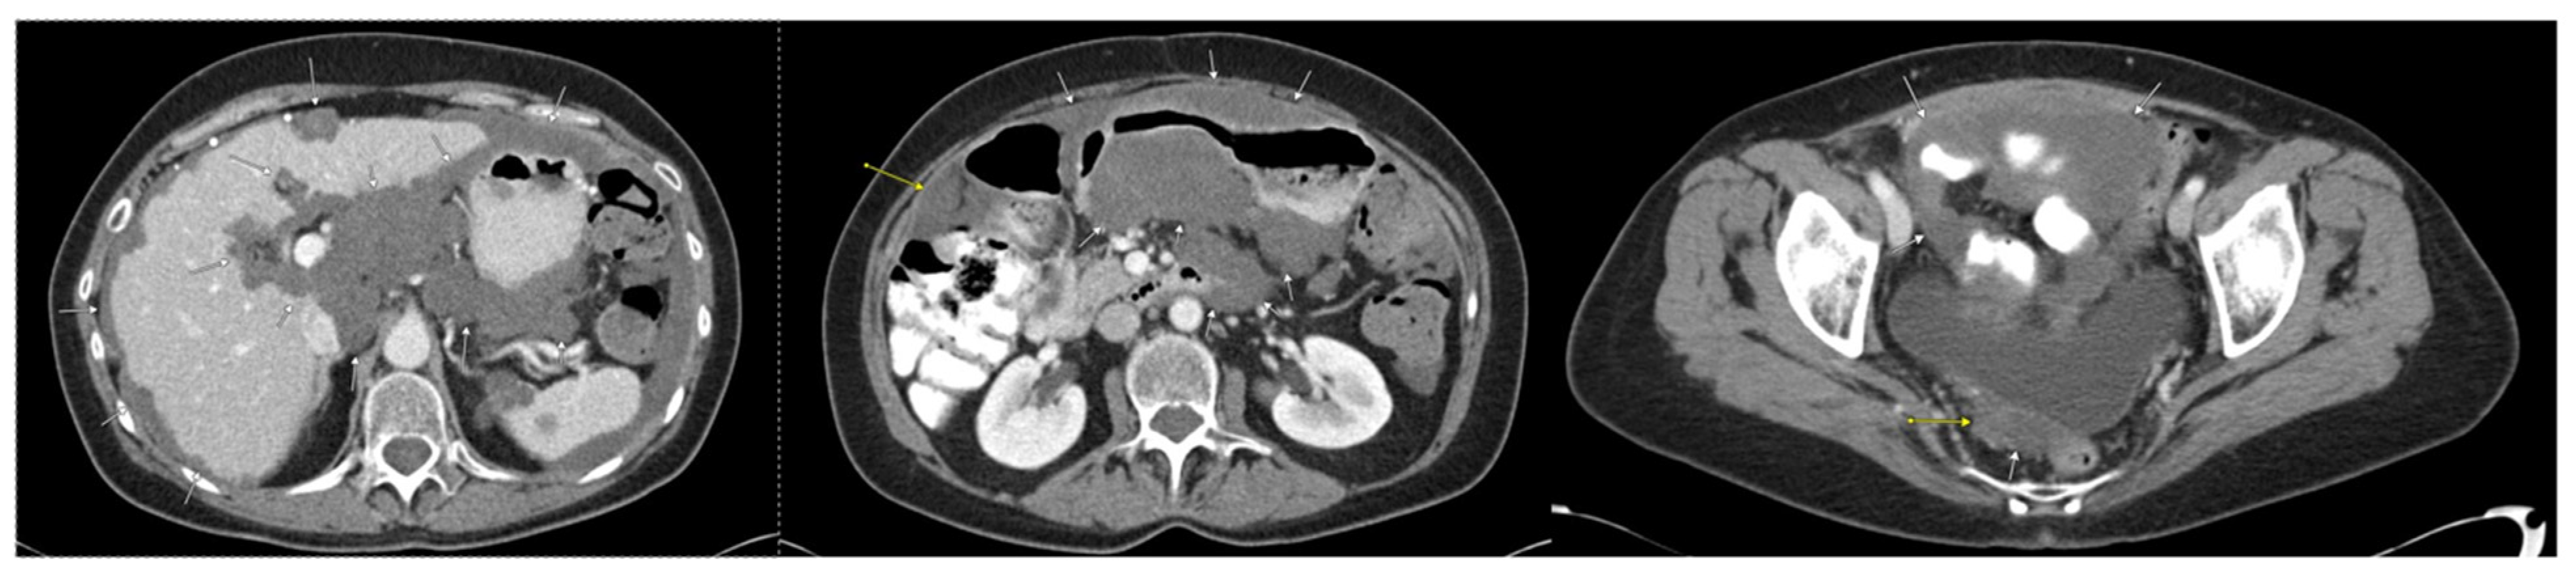

2. Case